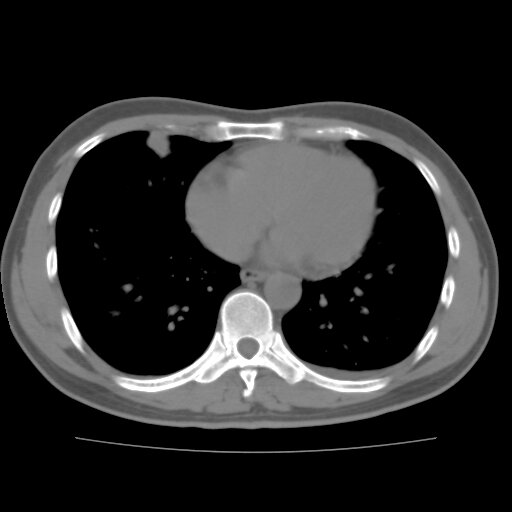

左侧胸痛,无其他病史

炎性假瘤

考虑肺内炎性肉芽肿,少量胸水。

转移瘤

考虑两肺感染性病变;建议抗炎治疗后复查。

暂考虑两肺感染性病变,左侧少量胸水;建议抗炎治疗后复查

首先考虑双肺感染性病变,左侧少量胸水,见过类似病例,抗炎后都吸收了

右侧胸膜下多发小结节——支持考虑:炎性假瘤!

警惕转移灶